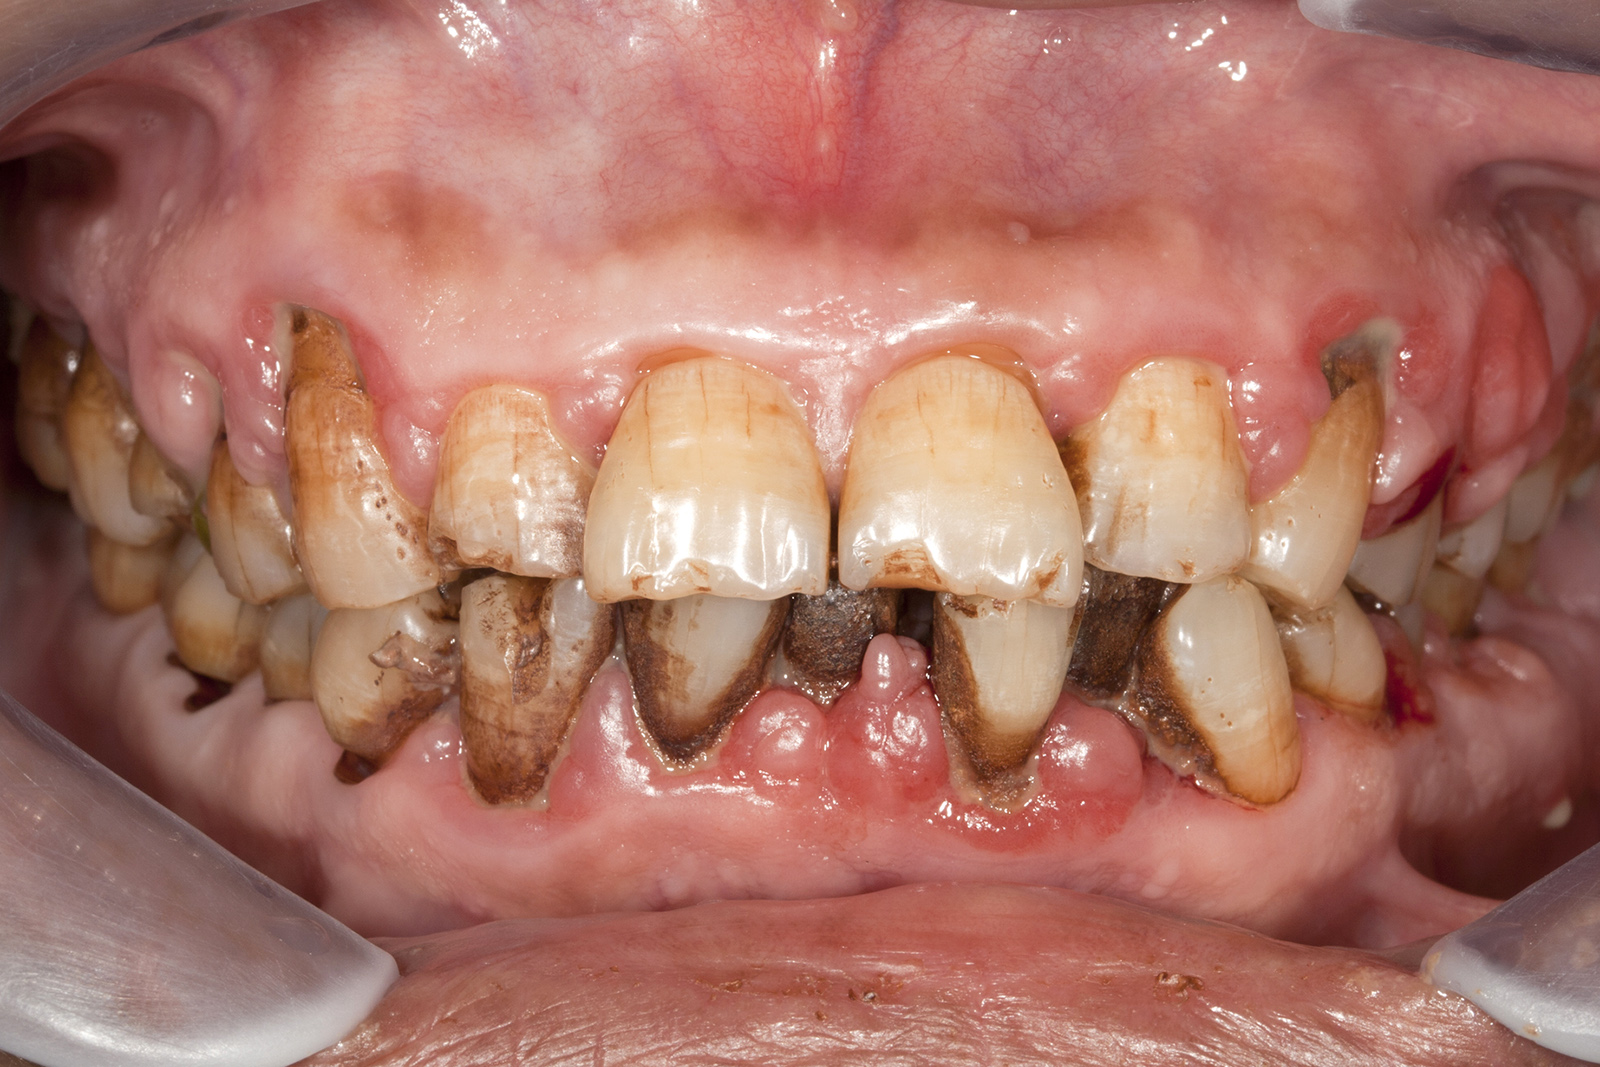

歯がボロボロの状態になってしまった患者さんには、それぞれに至った背景や理由があります。虫歯や歯周病になりやすい体質の方もいらっしゃいますが、多くの場合、過去の治療で感じた強い痛みや歯科医院でのつらい経験がトラウマとなり、歯科医院そのものが苦手になってしまったケースがほとんどです。その結果、治療を後回しにせざるを得なかった方も少なくありません。

だからこそ、今悩んでいる患者さんにお伝えしたいことがあります。たとえ歯がボロボロの状態であっても、適切な歯科治療を受けることで、美しく機能的な歯を取り戻すことは十分に可能です。